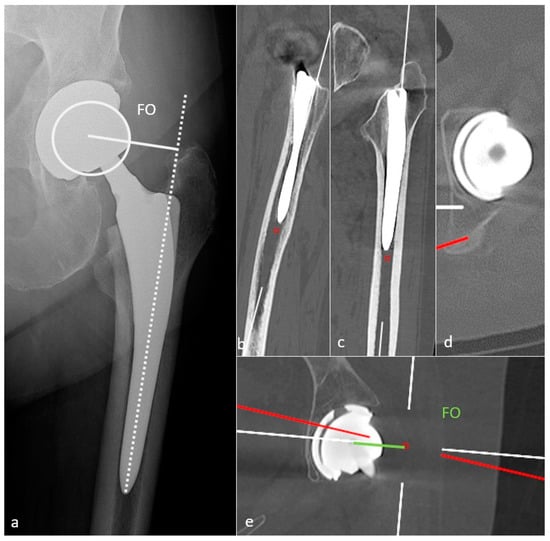

3.3.2. Femoral Side

| Femoral Offset | 41–44 mm (or similar to contralateral hip) | - Decreased: limping, mobility limitation, and dislocation by gluteal muscles weakness |

| - Increased: gluteal muscles pain and polyethylene wear | ||

| Femoral side | ||

| Femoral Stem position | Neutral or slight valgus | Periprosthetic fracture and stress reaction in case of varus |

| Femoral Neck Anteversion | 10–15° | - Increased: anterior dislocation and ischio-femoral impingement |

| - Decreased: posterior dislocation | ||

| Femoral Head | Centered or slightly inferiorly located | - Particle disease if located upwards (wear) |